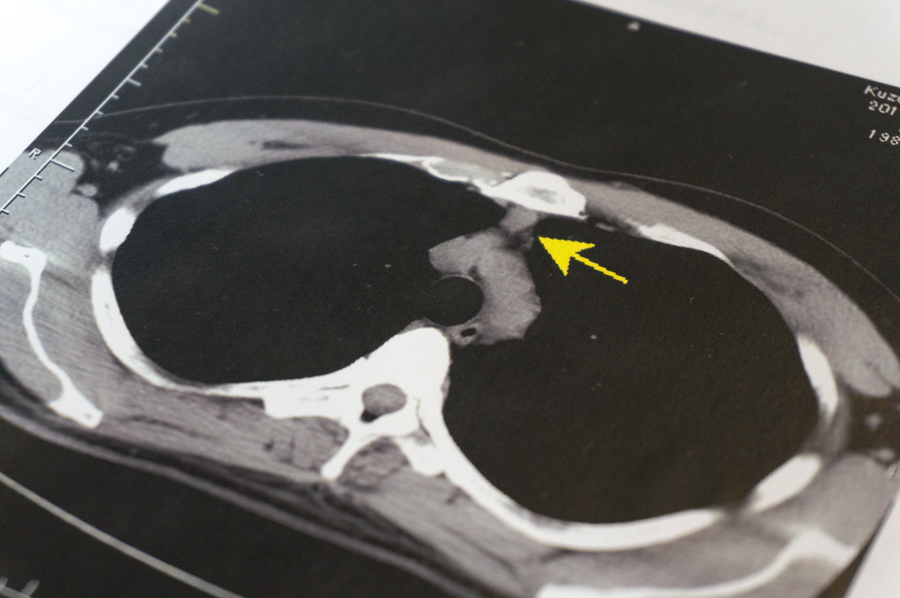

<胸腹部単純CT>

前縦隔に13mm大の結節病変がみられます。胸腺腫などの可能性もありますので、当院併設の呼吸器科受診をおすすめ致します。

こちらは心臓の上ぐらいの体の断面の画像。黄色い矢印のところにデキモノができてるそうです。それにしても画像全体を引いて見ると何となくサングラスにも見えます。

「胸腺腫」って何やろかと思って検索してみると、心臓の上ぐらいにある「胸腺」という部分に発生する腫瘍で、胸腺腫の患者の約30〜50%が、「重症筋無力症」という体の筋肉がすぐに疲れてしまい、ひどいとまぶたも閉じてきてしまうという病気を合併症として持っているのだそうな。コエー!

しかし、胸に何かできてるのは確かでも、胸腺腫かどうかはまだあくまで可能性。精密検査の結果次第です。